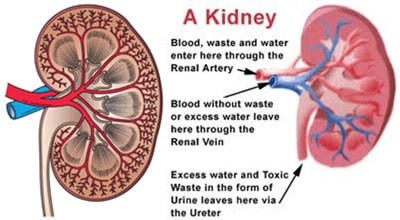

Πριν δούμε τι είναι ο καρκίνος νεφρού και οι μέθοδοι θεραπείας, ας δούμε πρώτα τα χαρατκηριστικά των συγκεκριμένων οργάνων.

Οι διαστάσεις των νεφρών είναι γύρω στα 11 με 12 εκατοστά και τα όργανα αυτά βρίσκονται κάτω από τα δύο μέρη του θώρακα, δεξιά και αριστερά της σπονδυλικής μας στήλης. Είναι πίσω από το έντερο και ακουμπούν στο οπίσθιο κοιλιακό τοίχωμα. O δεξιός νεφρός βρίσκεται λίγο πιο χαμηλά από ό,τι ο αριστερός νεφρός λόγω του ήπατος.

Οι νεφροί μέσω της ούρησης αποβάλλουν επιβλαβείς για τον οργανισμό ουσίες και έχουν τη συμβολή τους στη ρύθμιση της αρτηριακής πίεσης και των ηλεκτρολυτών (νατρίου, καλίου κλπ). Αυτό συμβαίνει αφού ο νεφρός είναι το όργανο που ρυθμίζει τη διακίνηση και επαναρρόφηση νερού, γλυκόζης και αμινοξέων, ουσίες μείζονος σημασίας για την ομαλή λειτουργία του οργανισμού μας.

Ένα επίσης πολύ σημαντικό χαρακτηριστικό των νεφρών είναι η παραγωγή ορμονών, όπως η ρενίνη, που είναι καθοριστική για την αρτηριακή πίεση, καθώς και η ερυθροποιητίνη, βασική ορμόνη παραγωγής των ερυθρών αιμοσφαιρίων του αίματος.